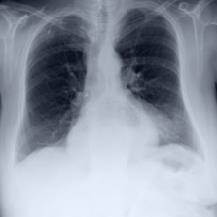

Thoracic disease detection from chest radiographs using deep learning methods has been an active area of research in the last decade. Most previous methods attempt to focus on the diseased organs of the image by identifying spatial regions responsible for significant contributions to the model's prediction. In contrast, expert radiologists first locate the prominent anatomical structures before determining if those regions are anomalous. Therefore, integrating anatomical knowledge within deep learning models could bring substantial improvement in automatic disease classification. This work proposes an anatomy-aware attention-based architecture named Anatomy X-Net, that prioritizes the spatial features guided by the pre-identified anatomy regions. We leverage a semi-supervised learning method using the JSRT dataset containing organ-level annotation to obtain the anatomical segmentation masks (for lungs and heart) for the NIH and CheXpert datasets. The proposed Anatomy X-Net uses the pre-trained DenseNet-121 as the backbone network with two corresponding structured modules, the Anatomy Aware Attention (AAA) and Probabilistic Weighted Average Pooling (PWAP), in a cohesive framework for anatomical attention learning. Our proposed method sets new state-of-the-art performance on the official NIH test set with an AUC score of 0.8439, proving the efficacy of utilizing the anatomy segmentation knowledge to improve the thoracic disease classification. Furthermore, the Anatomy X-Net yields an averaged AUC of 0.9020 on the Stanford CheXpert dataset, improving on existing methods that demonstrate the generalizability of the proposed framework.